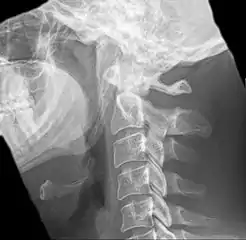

Anteroposterior and lateral radiographs of cervical spine showing ossification of the stylohyoid ligament on both sides

Imaging is important and is diagnostic. Visualizing the styloid process on a CT scan with 3D reconstruction is the suggested imaging technique.[12] The enlarged styloid may be visible on an orthopantogram or a lateral soft tissue X ray of the neck.